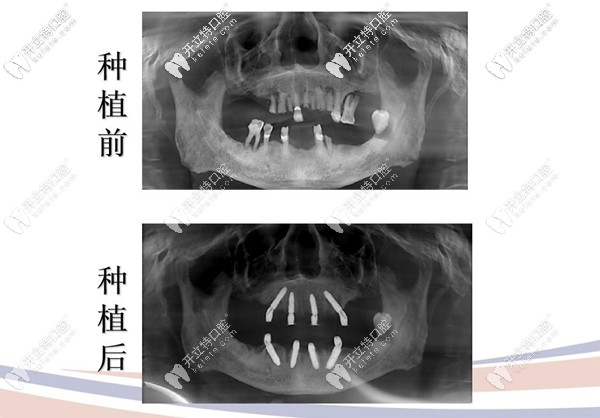

3、all on 4即刻種植案例。

74歲的王叔,全口無(wú)牙且缺失多年,牙周炎三度,烤瓷牙松動(dòng),口腔狀況糟糕;

種植牙前后拍片圖示

治療方案:拔除松動(dòng)牙,采用極光美式定制植牙All-on-4技術(shù),即刻種植,即刻修復(fù)當(dāng)天就能用哦!

顧客反饋:原來(lái)上下牙各用4顆種植體就可以恢復(fù)全口牙齒的咀嚼功能呀,這簡(jiǎn)直有點(diǎn)神奇,當(dāng)天就可以吃東西,真的是錢花哪哪舒服啊,“我”也挺滿意的。